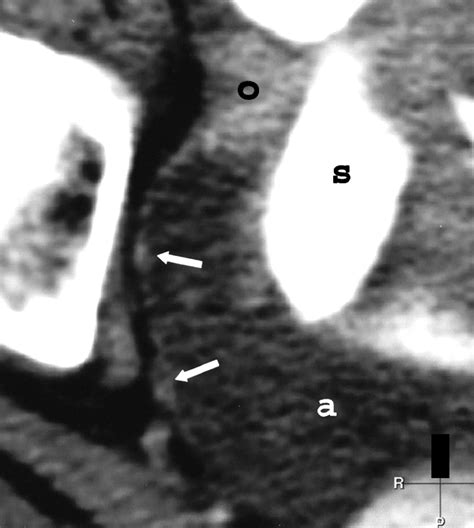

Diagnosing Papillary Serous Carcinoma usually involves a multidisciplinary approach. Because the symptoms, such as bloating, pelvic pain, or changes in bowel habits, can mimic less serious conditions, medical professionals rely on a combination of imaging and diagnostic procedures.

CT/PET Scans Used for staging and identifying metastasis.